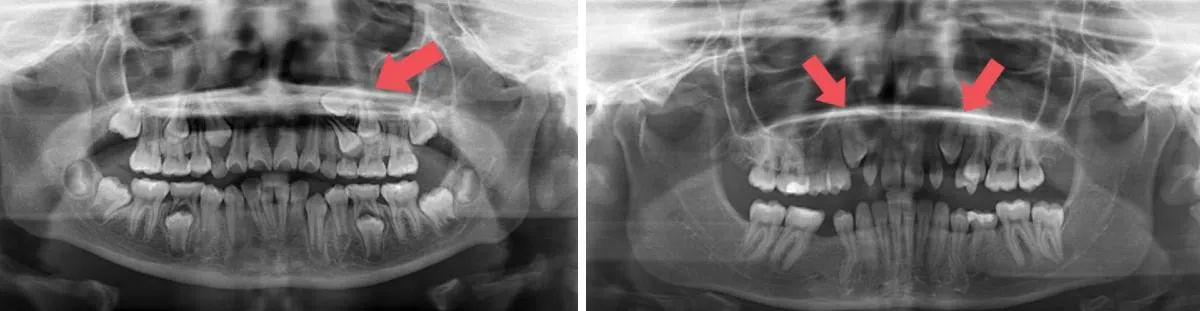

An x-ray will help determine whether the baby teeth are causing improper growth of the adult teeth, and in some cases, the affected baby teeth will be removed early to leave room for the adult teeth. This is one of the reasons why early orthodontic intervention can be extremely useful: The American Association of Orthodontists recommends children see an orthodontist by age 7.

X-rays help your orthodontist determine the position of the impacted teeth, even if you can ??t see it in your mouth.

If you have crowded teeth, it can be difficult to assess whether a tooth has grown in or not just by looking at your teeth: visiting an orthodontist is important since they can take x-rays to examine which teeth may not have grown in properly.